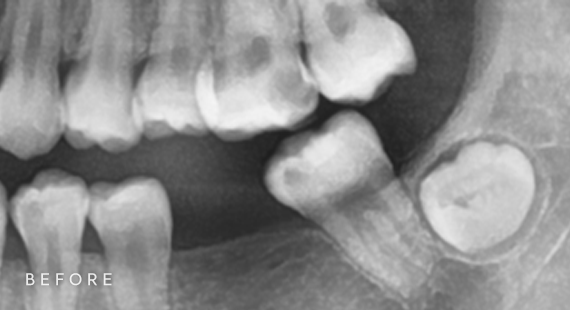

사랑니 발치